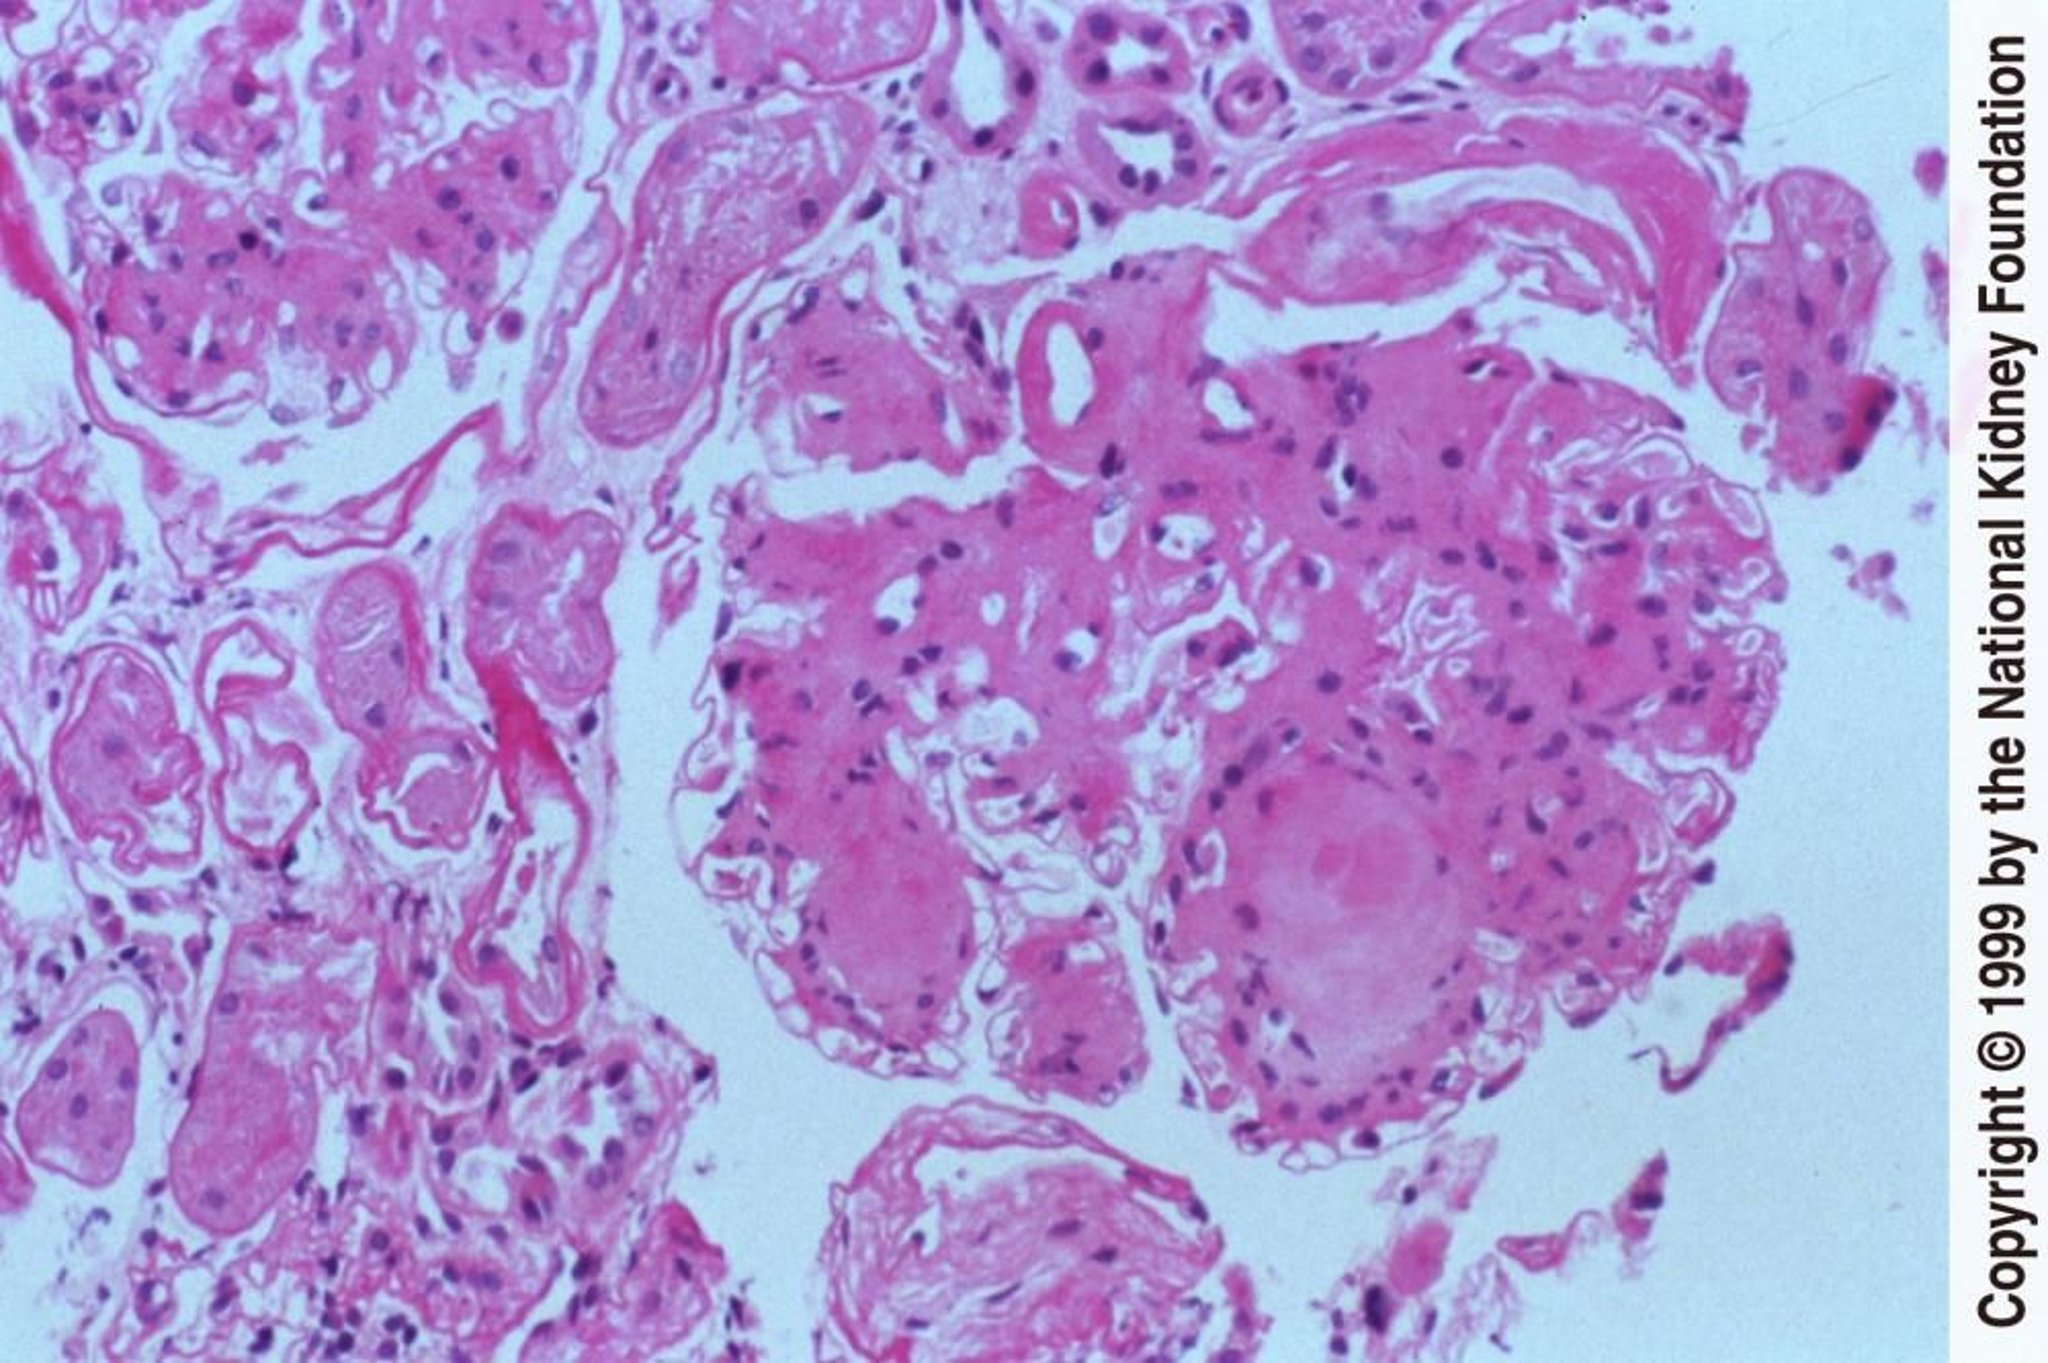

Bệnh thận do tiểu đường (nốt)

Hình thành các nốt không tế bào trong chất nền gian mạch là một đặc điểm khác biệt của bệnh thận do đái tháo đường (nhuộm axit-Schiff định kỳ, ×200).

Hình ảnh do bác sĩ Agnes Fogo và American Journal of Kidney Diseases' Atlas of Renal Pathology cung cấp (xem www.ajkd.org).